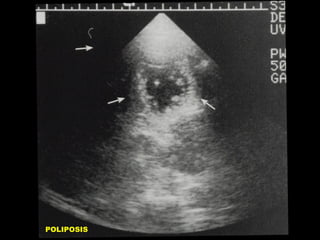

ADENOMIOMATOSIS

POLIPOSIS

POLIPOS DE COLESTEROL

• CAUSA MAS FRECUENTE DE ENGRO-

•

SAMIENTO FOCAL

MULTIPLES: COLESTEROLOSIS

ADHERIDOS A PARED VESICULAR

NO MOVILES

NO DEJAN SOMBRA ACUSTICA